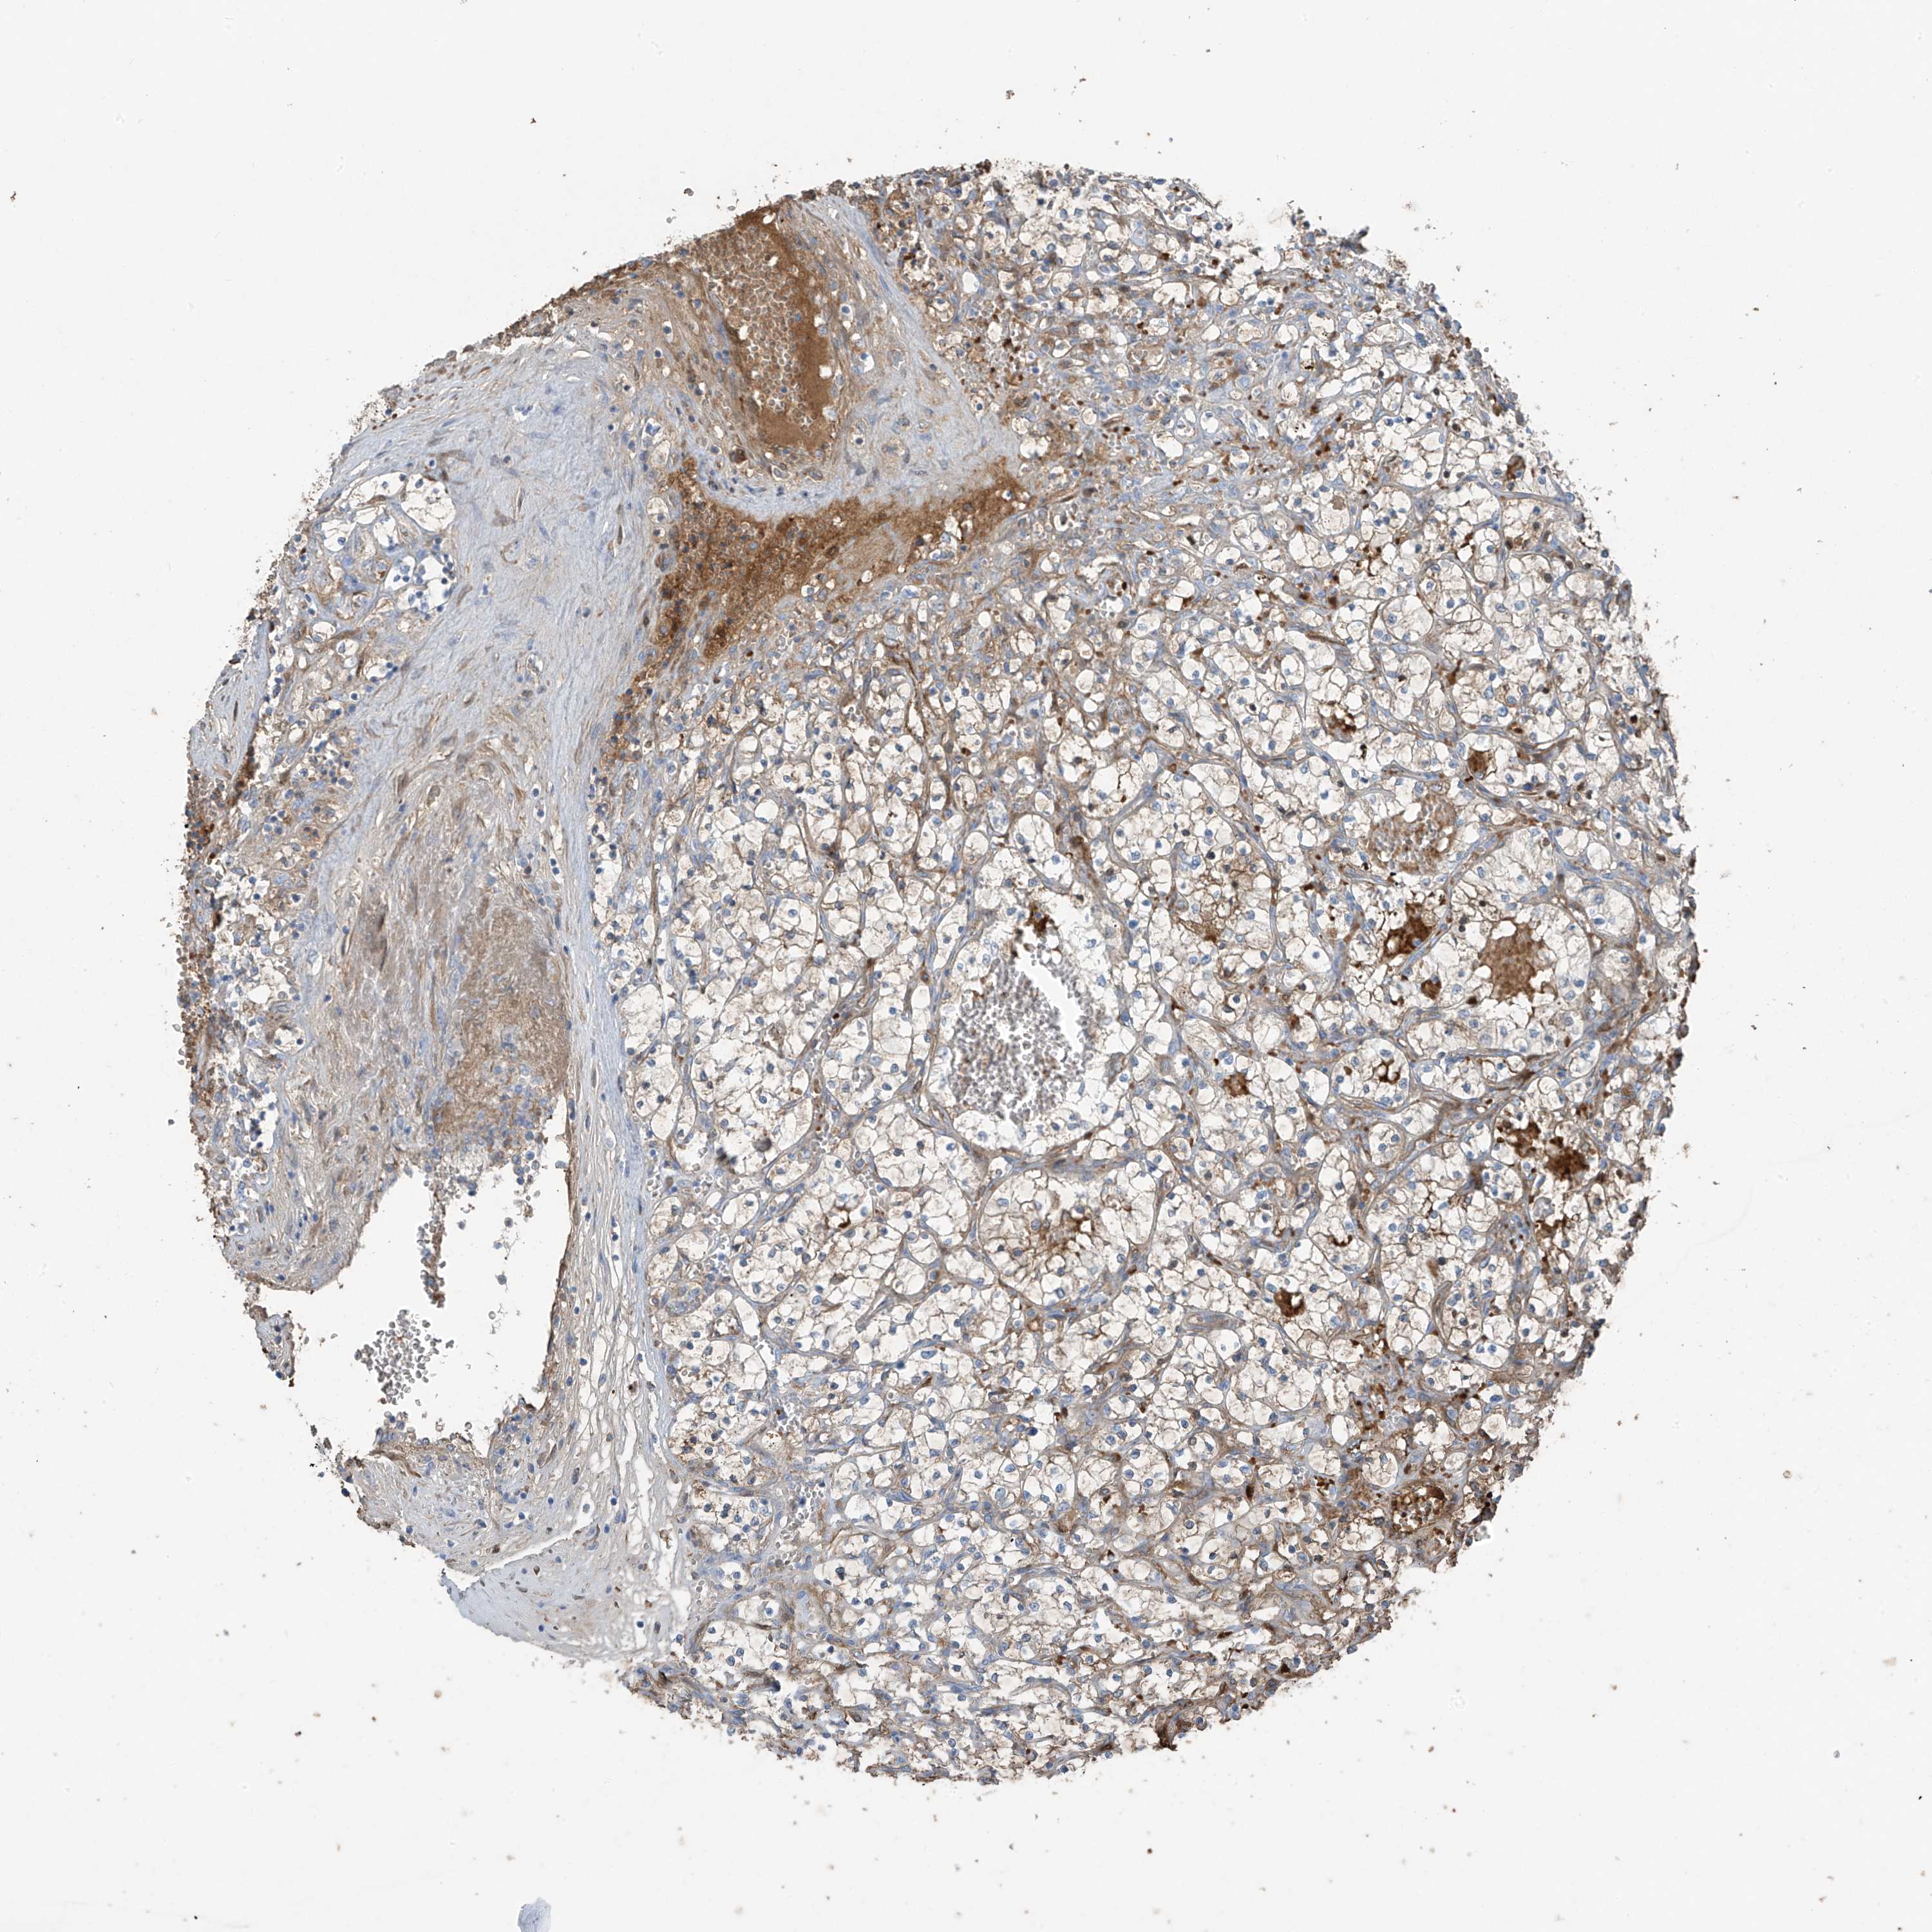

KIDNEY RENAL CLEAR CELL CARCINOMA (TCGA) - Interactive survival scatter ploti

The Survival Scatter plot shows the clinical status (i.e. dead or alive) for all individuals in the patient cohort, based on the same data that underlies the corresponding Kaplan-Meier plots. Patients that are alive at last time for follow-up are shown in blue and patients who have died during the study are shown in red.

The x-axis shows the expression levels (FPKM) of the investigated gene in the tumor tissue at the time of diagnosis. The y-axis shows the follow-up time after diagnosis (years). Both axes are complimented with kernel density curves demonstrating the data density over the axes. The top density plot shows the expression levels (FPKM) distribution among dead (red) and alive patients (blue). The right density plot shows the data density of the survived years of dead patients with high and low expression levels respectively, stratified using the cutoff indicated by the vertical dashed line through the Survival Scatter plot. This cutoff is automatically defined based on the FPKM cutoff that minimizes the p-score. The cutoff can be changed by dragging the vertical line or by entering a cutoff value in the square labeled "Current cut-off".

Under the Survival Scatter plot the p-score landscape (black curve; left axis) is shown together with dead median separation (red curve; right axis). Dead median separation is the difference in median mRNA expression between patients who have died with high and low expression, respectively. It is calculated as follows: median FPKM expression of dead patients with high expression - median FPKM expression of dead patients with low expression. This is intended to aid the user in visually exploring custom cutoffs and the associated p-scores and dead median separation.

Individual patient data is displayed and can be filtered by clicking on one or more of the category buttons on the top of the page. Categories describing expression level and patient information include: high, low, alive, dead, female, male and tumor stages. The scale of the x-axis can be toggled between linear and log-scale by clicking on the "x log" button. Mouse-over function shows TCGA ID, patient information and mRNA expression (FPKM) for each patient.

& Survival analysisi

Kaplan-Meier plots summarize results from analysis of correlation between mRNA expression level and patient survival. Patients were divided based on level of expression into one of the two groups "low" (under cut off) or "high" (over cut off). X-axis shows time for survival (years) and y-axis shows the probability of survival, where 1.0 corresponds to 100 percent.

PDGFC is validated prognostic, high expression is favorable in Kidney Renal Clear Cell Carcinoma (TCGA)

: 1.44

Average pTPM 4.0

Number of samples 521